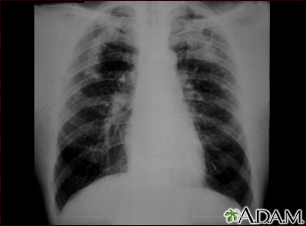

Coal workers pneumoconiosis, complicated